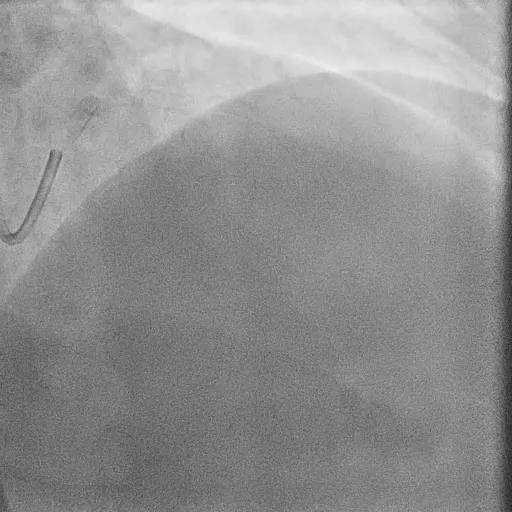

Post-DK Crush PCI

IVUS Findings:

Check the MSA at Ostial LAD and MSA at Ostial LCX with IVUS. Find underexpansion at Ostial LAD.

Use 3.5/15mm NC at LM-LAD and 3.0/15mm NC at LM-LCX for stent optimization.

Final results: Check the final DK crush results with IVUS. MSA: LM 12.1mm2, POC 11 mm2, Ostial LAD 8mm2, Ostial LCx 7.1 mm2